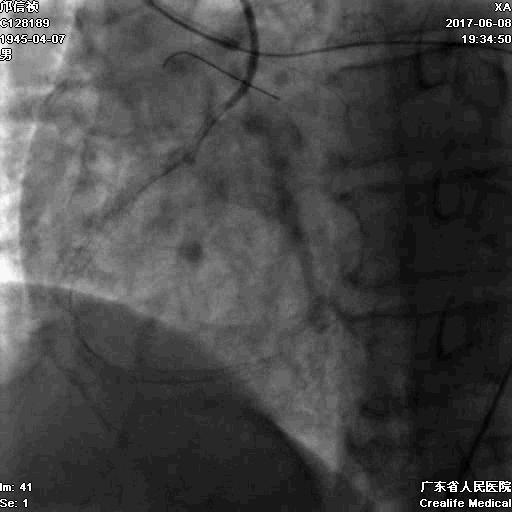

RRA:6F AL0.75 GC –RCA;

RFA:7F XB 3.5 GC—LCA 150cmcorsair

正向130cmFinecross微导管支持下尝试送PILOT150、Gaia 2导丝无法通过RCA闭塞段

SION导丝通过侧枝

逆向导丝:更换Gaia2

正向导丝:Gaia2,PILT150

正向导丝knuckle

2.5*15mm球囊扩张,逆向导丝尝试,但未能进入正向GC

1.正向2.5*15mm球囊扩张,Reverse CART

2.Guidezilla延长导管辅助下,逆向导丝进入正向GC